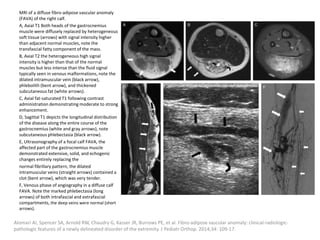

can then be treated with the sclerosant.

Müller-Wille R, Wildgruber M, Sadick M, Wohlgemuth WA. Vascular Anomalies (Part II): Interventional Therapy of Peripheral Vascular

Malformations [published online ahead of print, 2018 Feb 7]. Gefäßanomalien (Teil II): Interventionelle Therapie von peripheren

Gefäßmalformationen [published online ahead of print, 2018 Feb 7]. Rofo. 2018;10.1055/s-0044-101266.

Post-procedural care

Strict postoperative observation of the upper

airway is recommended after treatment of

patients with large cervical LMs.

Fever after injection of Picibanil can be treated